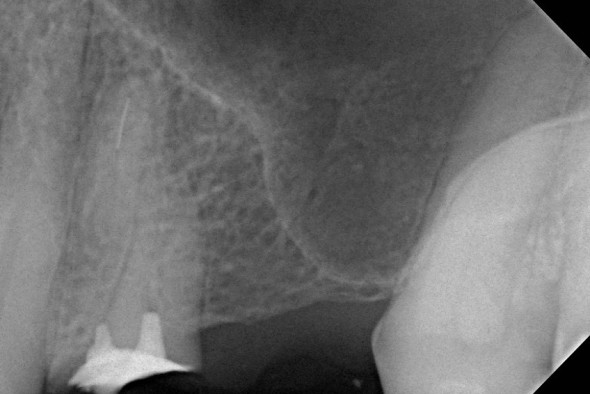

Der vierte Kanal –

doch keine Seltenheit

Nicht alle Zähne sind anatomisch gleich. Die Unterschiede gehen so weit auseinander, dass Zähne die drei Wurzeln haben sollten, manchmal doch vier oder sogar fünf Kanäle aufweisen. Oft bereiten wurzelbehandelte Zähne Beschwerden, weil sich in ihnen doch noch winzig kleine Kanäle verstecken. Wenn diese gefunden, gereinigt und desinfiziert werden, verschwinden auch die Probleme. Der Zahn ist gerettet.